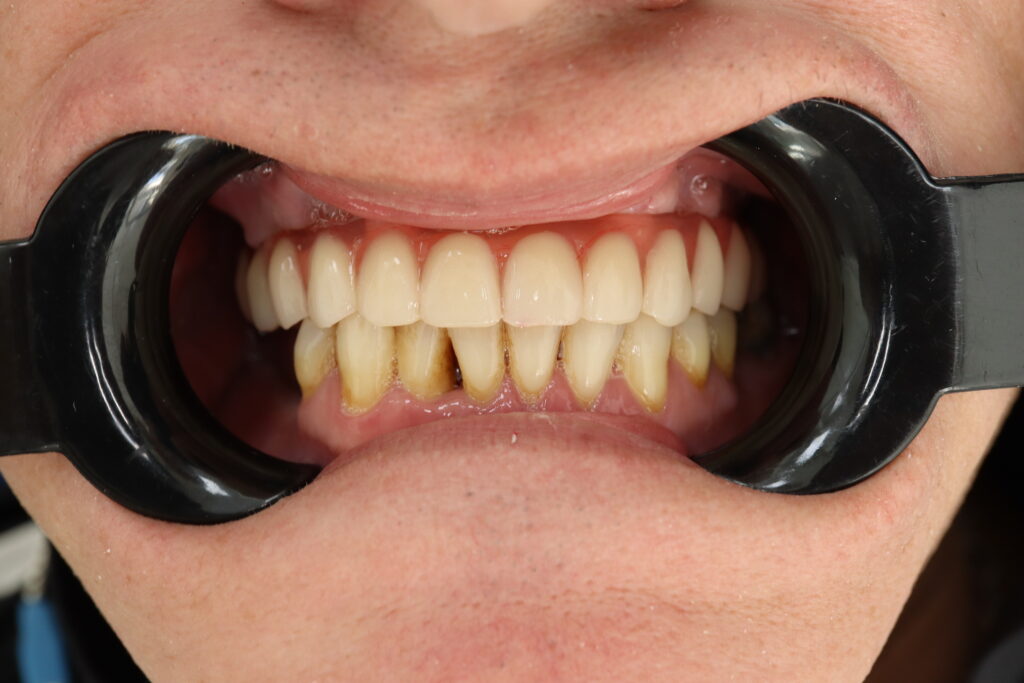

Ситуация до лечения

Жалобы: Пациент обратился к нам с целью проведения комплексной имплантации верхней челюсти.

Диагноз: Частичная вторичная адентия верхней челюсти.

пациент до протезирования